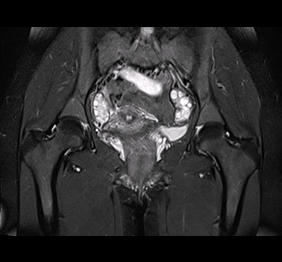

RMN cu instilare de gel

Examinarea pelvisului prin IRM cu protocol dedicat endometriozei permite analiza cu acuratete a tuturor structurilor anatomice pelviene, ceea ce ajuta la identificarea completa a organelor afectate si, implicit, la stadializarea cu acuratete a formelor de endometrioza 2, 3 si 4.